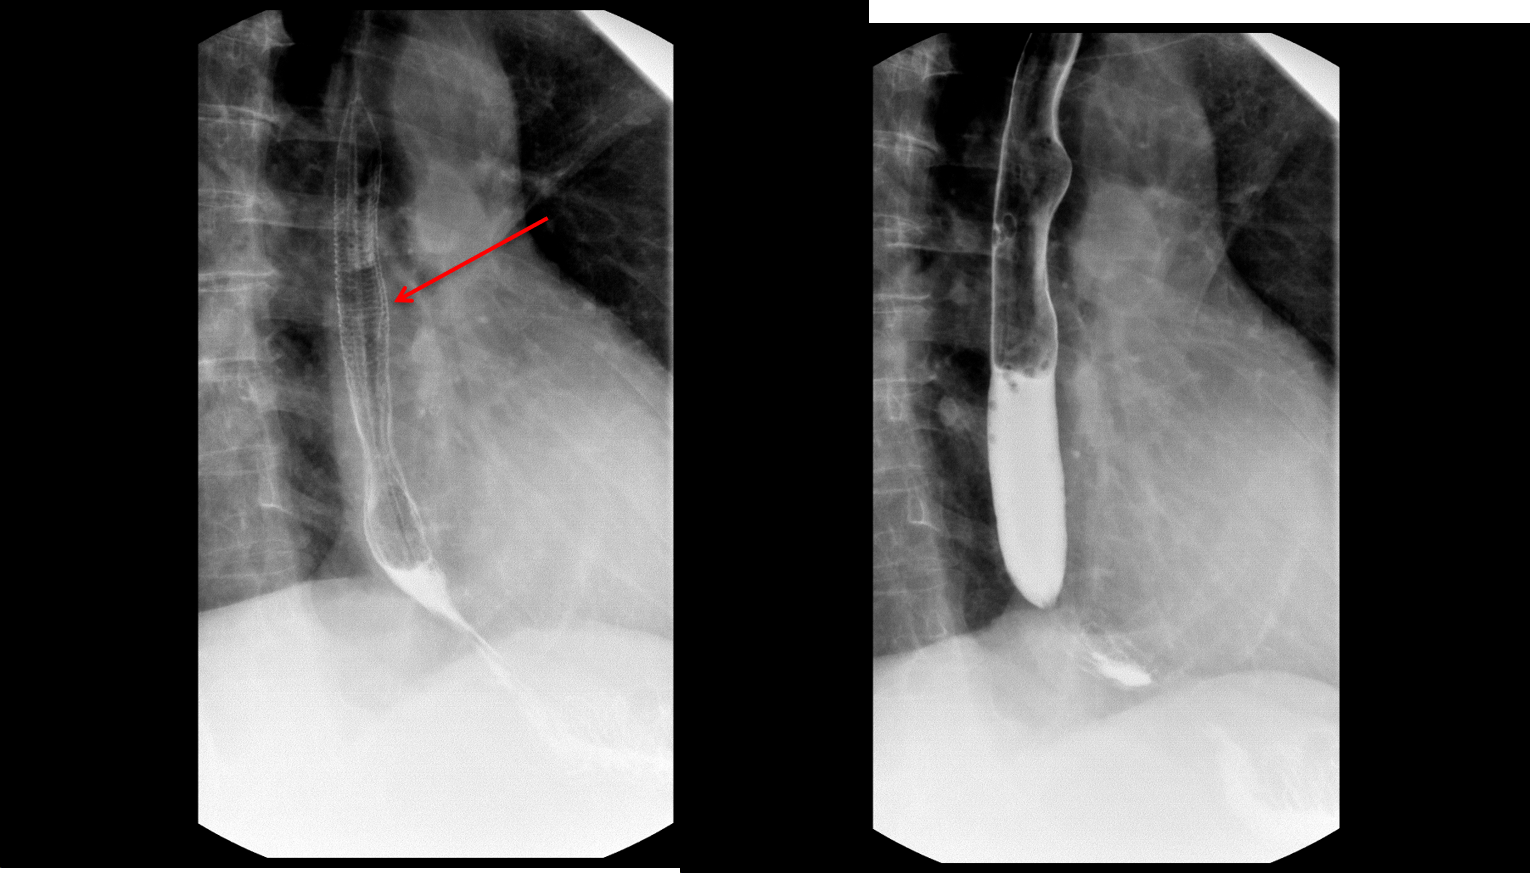

Esophagram shows fine circumferential folds (arrow) which do not persist and are not seen on the subsequent image.

Feline esophagus

- Transient, fine transverse folds in the esophagus

- Due to muscular contractions

- Does not persist

- Almost always seen in the setting of gastroesophageal reflux